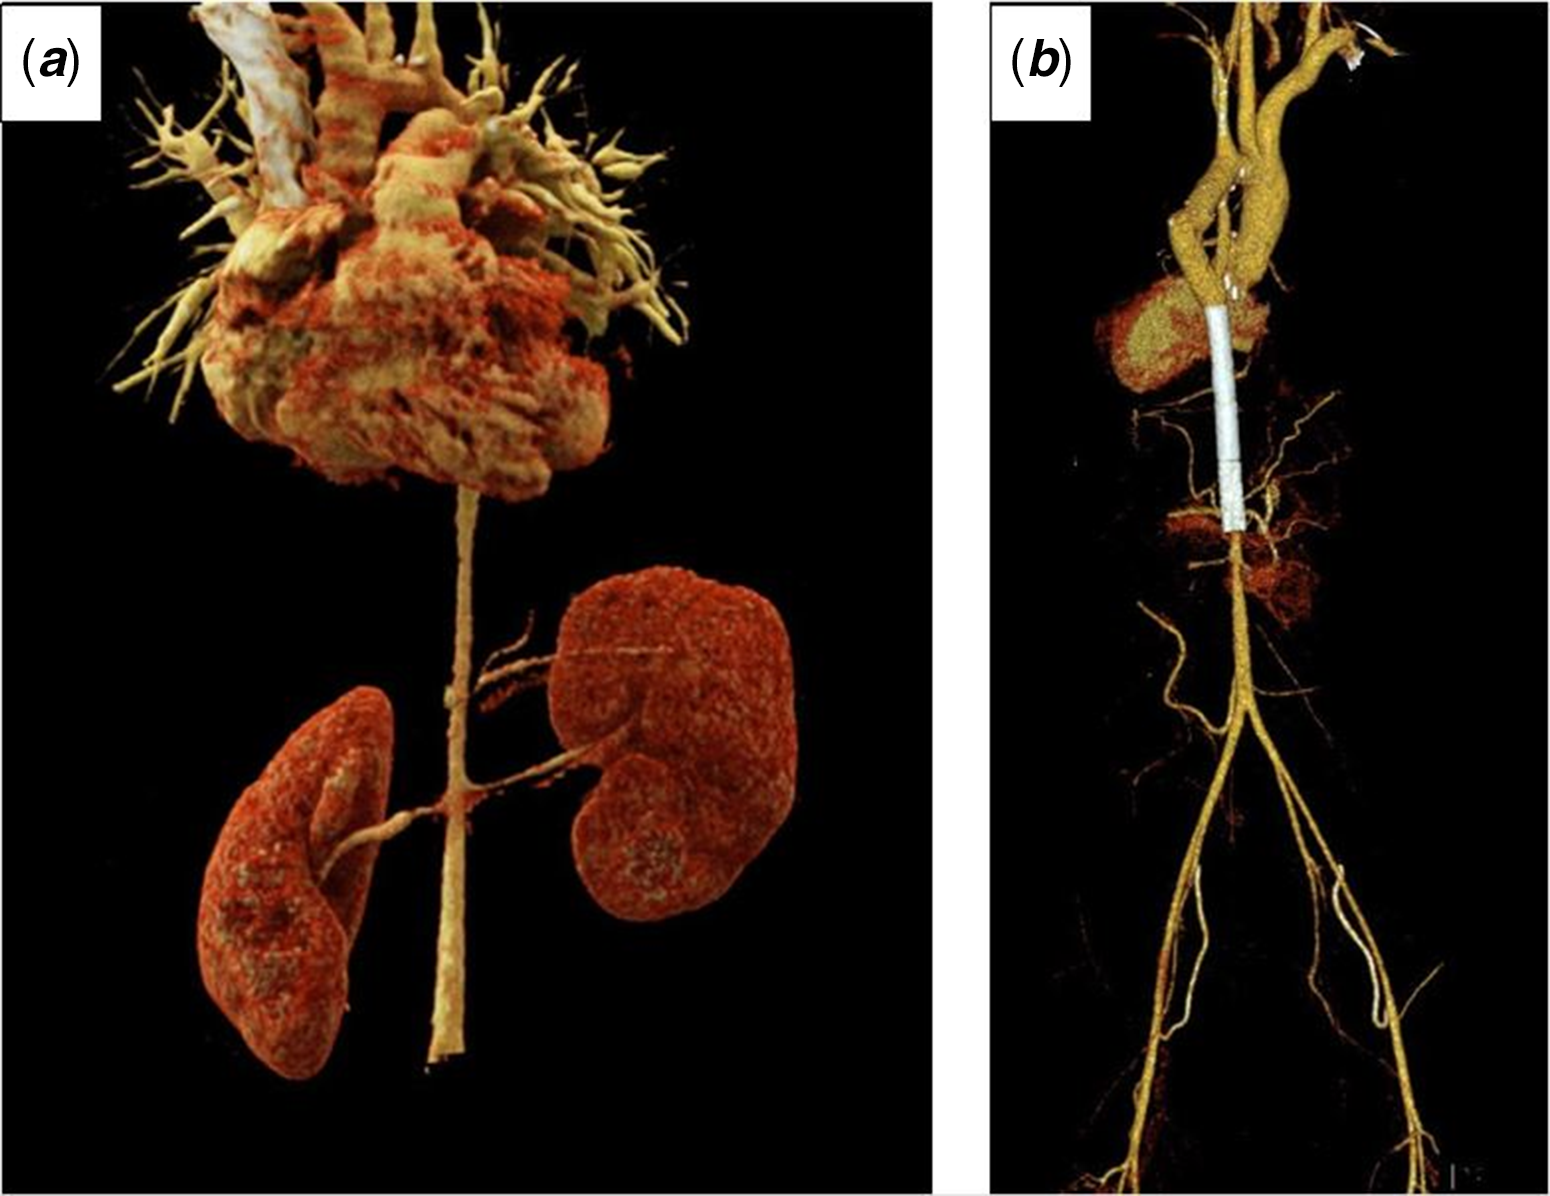

Ambulatory blood pressure was measured for 24 hours and presented high blood pressure values during the day (151/70/93 mmHg) and night (154/70/94 mmHg), despite using antihypertensive treatment. To determine the aetiology of hypertension and to evaluate the operated coarctation area, CT angiography was performed as a next step. The graft and the native aorta were observed in the coarctation area. Lumen was patent. In this process, the diameter of the native aorta was measured as 5 mm. CT angiography also showed a diffuse severe narrowing of the distal thoracic and proximal abdominal aorta up to the infrarenal level (Fig 1a). A narrowing was observed at the proximal level of the right renal artery.

Figure 1. CT angiography with 3D reconstruction images of the patient before ( a ) and after ( b ) stent implantation.

After the procedure, the patient’s hypertension regressed. CT scan revealed (Fig 1b and b) a short part of the distal abdominal aorta still hypoplastic. One year after the procedure, the patient did not complain of any symptoms, and her blood pressure remained normal.